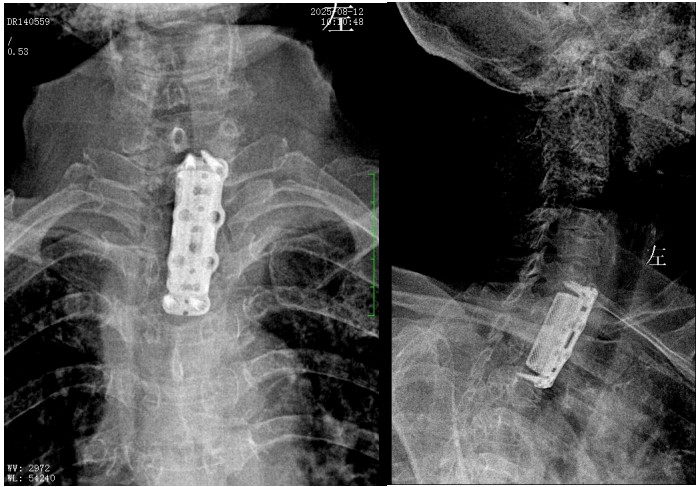

錢軍博士組織團(tuán)隊進(jìn)行了詳盡的術(shù)前討論,充分的術(shù)前準(zhǔn)備后,于8月10日為患者實施了“前路病灶清除、人工椎體植入、植骨融合內(nèi)固定術(shù)”。順利完成了徹底清除病灶,椎管減壓解除脊髓壓迫,矯正后凸畸形,重建脊柱穩(wěn)定性的手術(shù)目標(biāo)。

術(shù)后,脊柱外科醫(yī)護(hù)團(tuán)隊為病人制定了快速康復(fù)方案,經(jīng)過精心治療與護(hù)理,李奶奶訴胸背部、雙上肢的疼痛癥狀較前明顯好轉(zhuǎn),晚上終于能睡個安穩(wěn)覺了。兩周后,李奶奶恢復(fù)良好,現(xiàn)已順利出院。